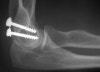

치료

대개는 수술적으로 치료해야 합니다.

치유과정에서 진통, 골 유합의 촉진을 위해 침 치료를 적용합니다(근위축 예방과 근육 운동시의 동통완화 효과를 목적으로 합니다).

수술 후 조기에 능동적 관절 운동을 실시하여야 하지만 관절에 부하가 가해지는 운동(특히 회외전)은 금지합니다.